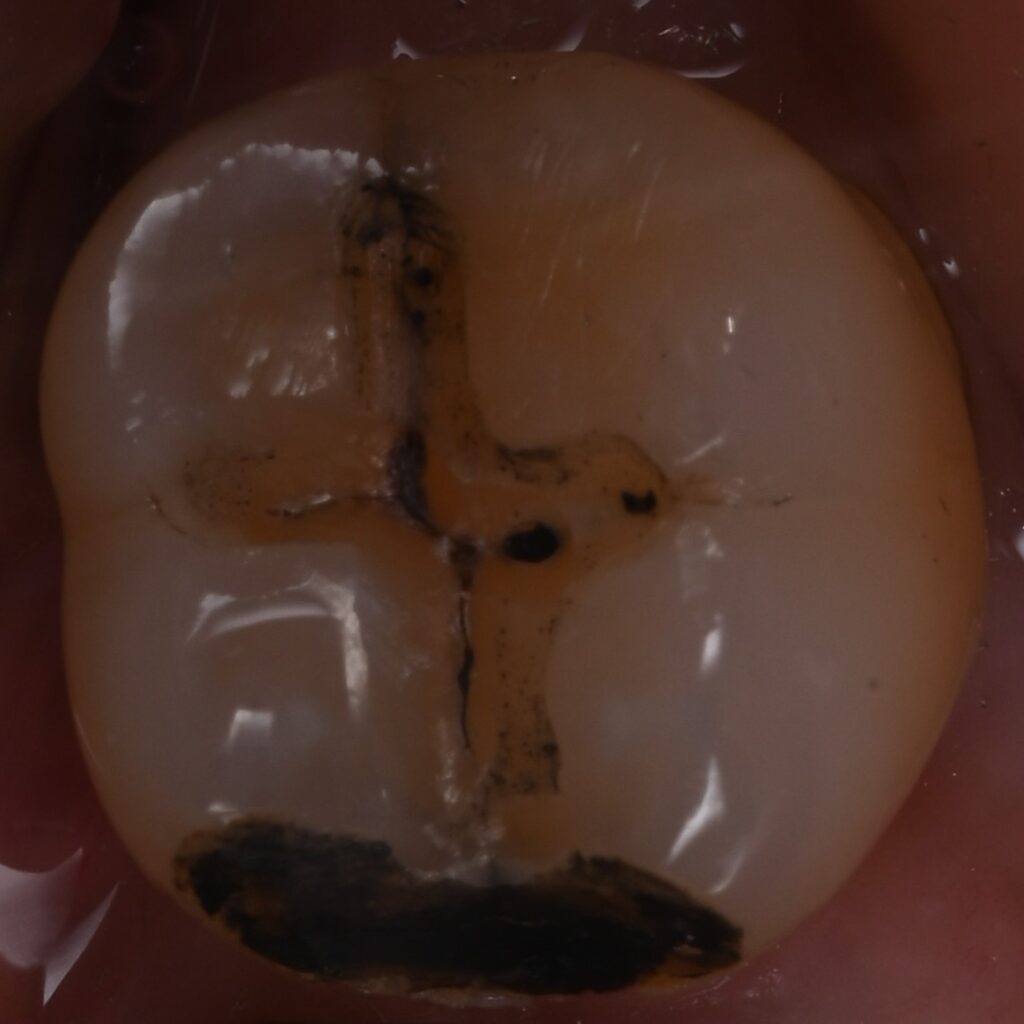

奥歯の大きなむし歯を1日で修復|ダイレクトボンディングによる審美修復

| 治療内容 | 右下7番に大きなむし歯が認められたため、ラバーダム防湿下でむし歯を除去し、コンポジットレジンによるダイレクトボンディング修復を行いました。 歯を大きく削ることなく、天然歯の形態や咬合を再現するよう丁寧に積層し、自然な見た目と機能の回復を目指しました。 |

| 治療期間・治療回数 | 1日 / 1回 |

| 治療費用 | ダイレクトボンディング修復 ¥66,000(税込) ※自由診療 |

| リスク・副作用 | ・経年的に着色や摩耗が生じる可能性があります ・強い咬合力や歯ぎしりにより欠ける可能性があります ・むし歯の進行状況によっては将来的に再治療が必要になる場合があります ・咬合の状態によってはナイトガードの使用をおすすめすることがあります |

| 備考 | 本症例ではラバーダムを使用し、唾液や湿気を遮断した清潔な環境下で接着処置を行っています。 ダイレクトボンディングは歯を必要以上に削らず修復できる低侵襲な治療方法であり、適切な症例では1日で機能回復が可能です。 |